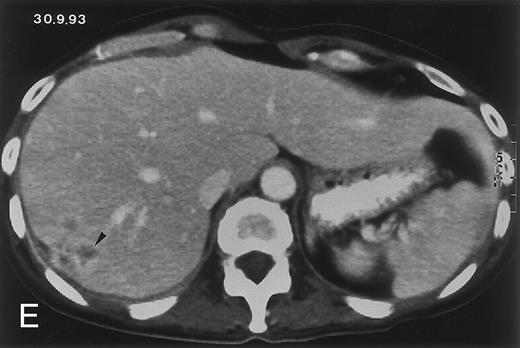

Radiologic evolution in patient A. (A) Postcontrast abdominal CT scan on March 16, 1993 shows multiple small hypodense areas in all segments of the liver, suggestive of hepatic candidiasis. Seven days previously, the patient had recovered from severe neutropenia after the first cycle of chemotherapy for AML. (B) On April 23, 6 days after the neutrophil count had dropped below 500/μL in the second cycle of chemotherapy, there is no evidence of focal lesions on postcontrast CT scan. (C) On June 18, when neutrophils were normalized for 46 days, CT scan again shows multiple small abscesses.

(D) On August 23, 15 days after the neutrophil count had dropped below 500/μL in the third chemotherapy cycle, focal liver lesions clearly decreased in size and number. (E) On September 30, 35 days after neutrophil recovery, multiple hepatic abscesses are seen (arrowhead). To show maximal extent of lesions the scan shown is at a slightly different level. (F) On June 16, 1994, 230 days after neutrophil recovery, the CT scan has normalized.